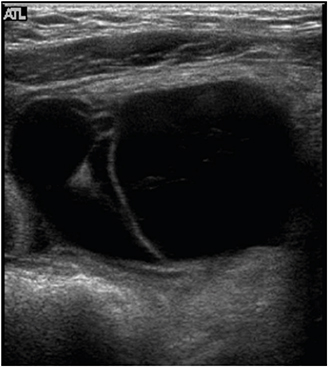

All patients underwent abdominal ultrasonography and computed tomography (CT) scans. In patient No. 7, these modalities showed a cystic mass, 9 cm in size, with multiple septa in the lower abdomen (Figs. 1, 2). An abdominal CT scan of patient No. 9 showed a huge multiloculated cystic mass with a septum; this mass occupied nearly the entire abdominal cavity and caused the displacement of the bowel to the left posterior abdomen.

Fig. 1

Abdominal ultrasonography of patient No. 7, showing a hypoechoic cystic mass with an ovoid wall, separated by intracystic septation in the lower abdomen.

Abdominal lymphatic malformations are very difficult to diagnose before surgery, with most patients diagnosed by postoperative biopsy. No specific radiologic findings can confirm abdominal lymphatic malformations before surgery. Abdominal ultrasonography or CT is necessary for accurate diagnosis before surgery, with these modalities providing information on lesion location and size and association with adjacent lesions. On abdominal ultrasonography, these lesions appear as hypoechoic cystic masses with a round wall separated by echogenic septa in the cystic space [37]. Abdominal CT scans provide more information before surgery about lesion location, size, and association with adjacent lesions. Typically, shading of the contents is homogeneous, with CT scans showing a single or polycystic mass with thin walls, as well as showing the relationship of the lesion with adjacent organs and blood vessels [319]. Abdominal magnetic resonance imaging (MRI) does not provide more information than ultrasonography or CT about lesion location, but it may be helpful in diagnosing complications such as hemorrhage. CT scanning is useful diagnostically, but ultrasonography and MRI may be better for children because of low radiation exposure. The differential diagnosis of abdominal lymphatic malformations includes other cystic abdominal masses, such as choledochal cysts, urachal cysts, ovarian cysts, renal cysts, intestinal duplications, abdominal lymphoma, simple mesenteric cysts, and pancreatic pseudocysts [82021].